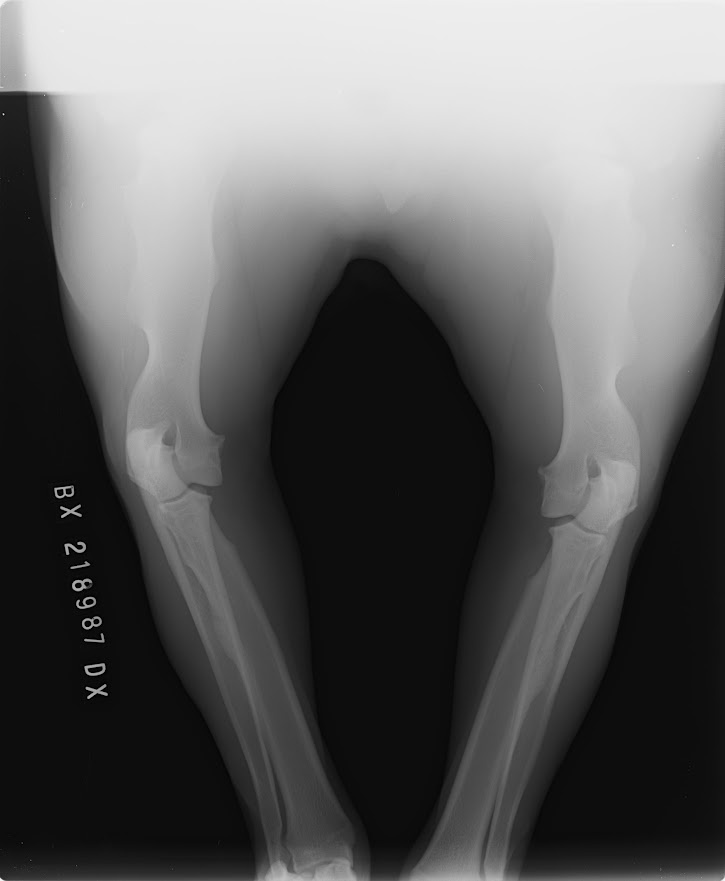

Hledáme nevěstu pro mladého psa BD s PP, Butch Coolidge dei Mastini del Goya, import Itálie, DKK AA, DLK 00, srdce OK, vyšetření sperma, vynikající pohyb, V1, CAC, Národní vítěz ČR, stáří 3 roky, perfektní povaha